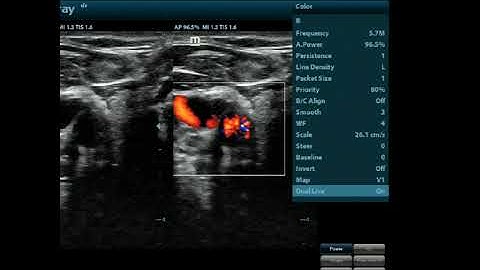

How to use dual screen on the Mindray Z60